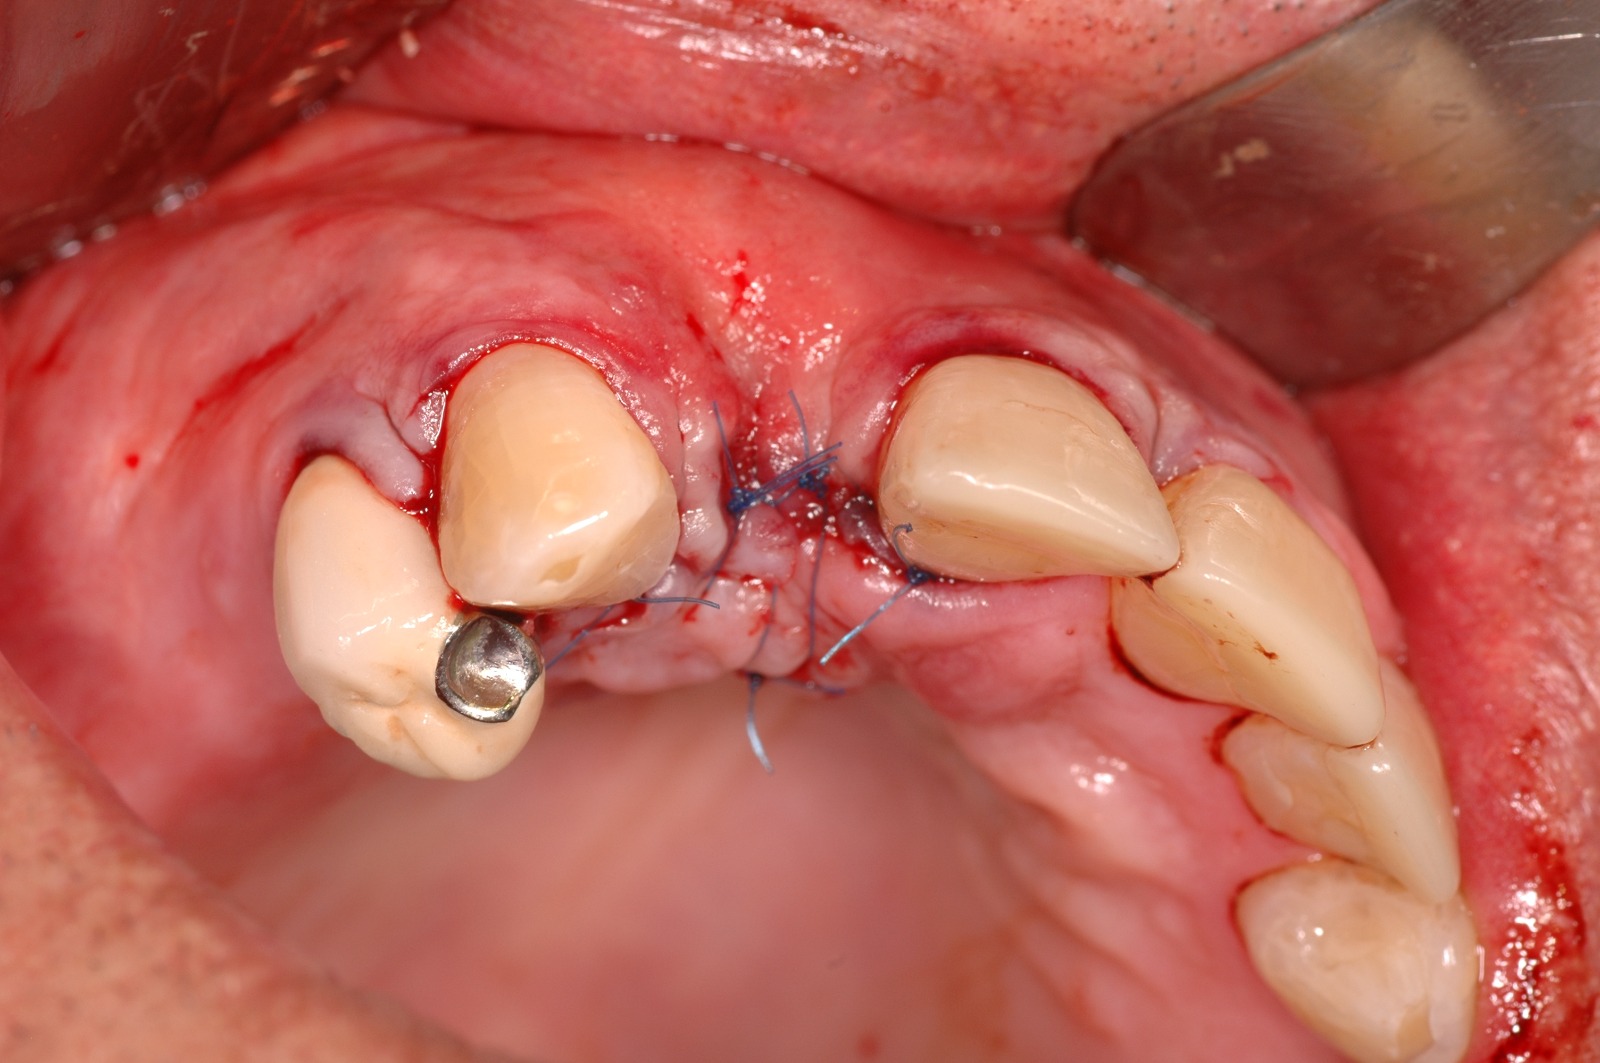

Regeneración ósea guiada

En algunos casos, puede ser necesario realizar un injerto óseo antes o durante la colocación de los implantes dentales. Esto se debe a que la cantidad o calidad del hueso puede no ser suficiente para soportar el implante de manera adecuada.

Casos Clínicos

Observa cómo la ciencia y la tecnología se unen para reconstruir el hueso perdido y devolver la confianza a quien la había perdido